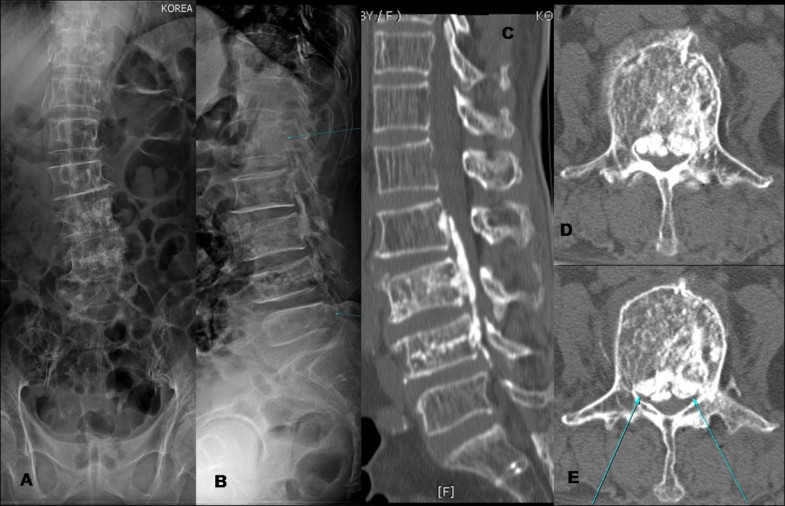

Back surgery might be an option if conservative treatments haven't worked and your pain is persistent and disabling. They are very well tolerated by the dental tissues. Your surgeon puts cement into your broken bones to help keep your spine stable.

Compression of spinal nerves caused by arthritis or scoliosis vertebroplasty, which is the injection of bone cement into compressed vertebrae. A couple of months later i developed terrible back pain after getting into a chair to have my eyebrows done. Thanks to new and innovative techniques there has been a revolution in back and neck surgery. 41:30 the frcs mentor 3 612 просмотров.